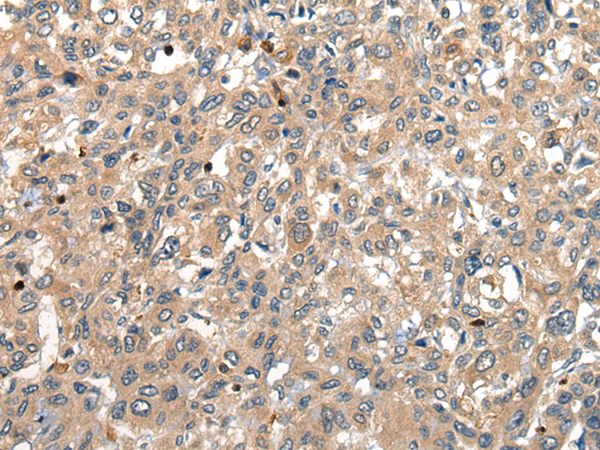

IHC positive control: |

Human liver cancer |

IHC Recommend dilution: |

25-100 |